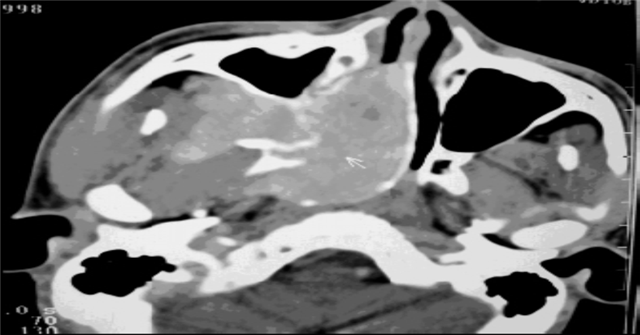

图2 MRI 横断增强:肿瘤信号均匀强化, 边界清(图片来源于医院影像中心)

图3、CT 横断位: I肿瘤鼻腔, 骨质无破坏, 增强病灶明显强化(图片来源于医院影像中心)